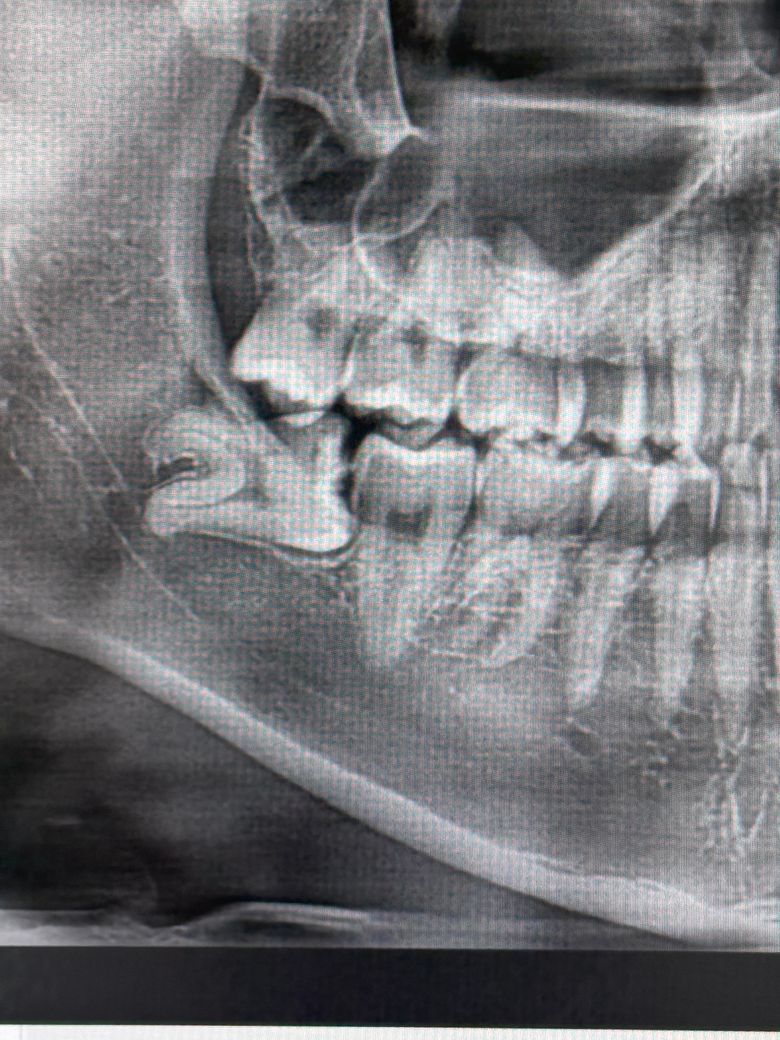

사랑니 옆 어금니의 검은부분 충치일까요?

매복 사랑니 옆쪽 어금니 측면에 저 검은 부분이 인접면 충치일까요?

엑스레이로 이런 인접면 충치를 판별 할 수 있는 지도 궁금하고

만약 맞다면 어느 정도로 치료를 해야할까요?

• 1번 째 사진

치아가 겹쳐 잇기 때문에 저부분은 사랑니 발치를 하고나서 다시 엑스레이를 찍어서 확인해보셔야될것같습니다.

1. 두번째 엑스레이 기준으로 보면 사랑니 옆 어금니의 옆면 충치는 다소 명확히 보입니다. 또한 사랑니와 어금니 사이 음식물이 끼어 충치가 유발되었을 것으로 강력히 의심됩니다.

1. 저런 경우는 일단 사랑니 발치 후 옆면 충치에 대한 접근이 가능한지 봅니다. 옆구리 쪽으로 접근이 가능한 경우도 있고 힘든 경우 그냥 위에서부터 파고 내려가고 인레이 내지는 크라운을 씌워주게 됩니다.

2. 엑스레이로 보기에는 충치가 다소 크고 깊어서 옆쪽으로 접근은 어려울 수도 있을 것 같습니다.

사진 상에는 겹쳐보이는 것이기 때문에 사랑니 뽑고 다시 찍어봐야 하며 가능성은 있어보입니다.